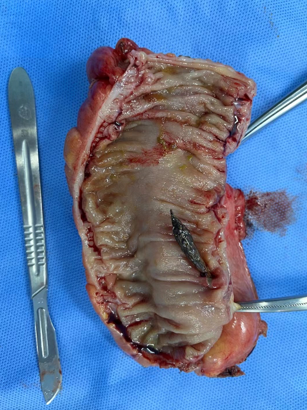

老太太被送入手術室,在急診全麻下行腹腔鏡剖腹探查手術,大腸外科李軍主任醫師透過精湛的技術,找到了導致腸穿孔的罪魁禍首——一顆小小的棗核。

手術中,李主任發現穿孔位於乙狀結腸下段,距離直腸肛門很近,在穿孔部位以上部分節段腸管已經出現缺血壞死,穿孔處周圍有積液,並有腹膜炎症表現。手術進行約2小時,切除了穿孔及缺血段腸管,並放置了兩根腹腔引流管引流炎症性腹腔積液,術後安返ICU,轉危為安。